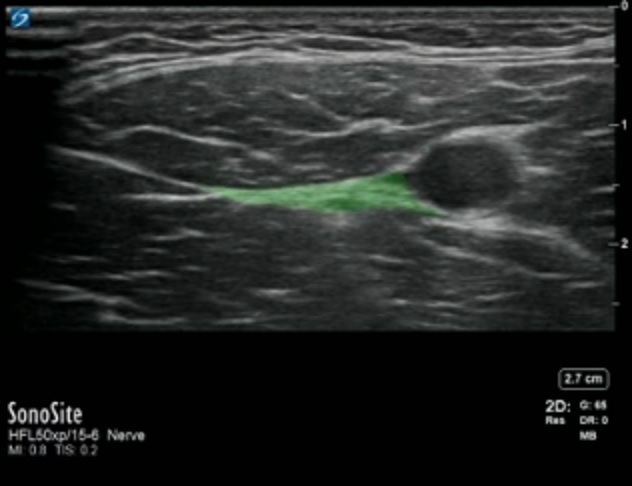

Highlighted Area: Fascia Between Sartorius Muscle and the Vastus Medialis Muscle Image